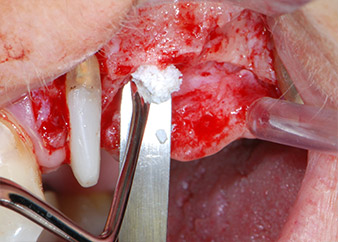

One month later, on the day of surgery, pain and inflammation at tooth 24 were minimal, but mobility of Miller class 2 was still present. After opening the flaps and cleaning the periapical and peri radicular infected tissue, the extent of the bone defect became obvious (Figs. 2 and 3).

At the buccal root, all vestibular and distal bone was missing. Attachment was essentially restricted to the palatal root, underlining the preliminary poor prognosis. Tooth 27 also showed a reduced horizontal attachment and a minimal apical rarefaction (cf. Fig. 1) without clinical symptoms.

total loss of bone and attachment

Fig. 2 and 3: After raising flaps, one month after endodontic revision and initiation of full-mouth periodontal therapy, the buccal root of tooth 24 showed a total loss of bone and attachment.